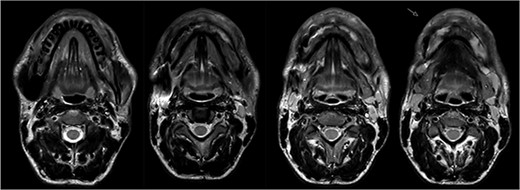

In 2020, a 99 m Technetium scintigraphy was performed to rule out disseminated osteomyelitis. The scintigraphy showed no other foci of enhancement but the mandible with increased inflammatory activity in the anterior portion of the jaw (Fig. 1). Magnetic resonance imaging (MRI) was performed to analyze the localization and extent of the disease. In Fig. 2, a high inflammatory activity, resembled by a strong local enhancement in the T2 weighting, was seen, reaching from the right condyle to the left. Cone beam computed tomography (CBCT) confirmed a widespread patchy radiolucency extending to both left and right mandibular condyles (Fig. 3). Hard tissue biopsies were taken to rule out malignancy due to the disease’s extensive destruction and chronic course. Blood assays were also requested.

Magnetic resonance imaging (MRI) before bisphosphonate therapy (axial sections). T2 weighting of the MRI shows the high inflammatory activity especially in the anterior portion of the mandible (arrow).

The MRI performed three months after the last pamidronate infusion revealed a significant reduction of enhancement in the mandible with some patchy hypointense areas remaining (Fig. 5).

Magnetic resonance imaging (MRI) 3 months after bisphosphonate therapy. T2 weighting shows the significant reduction of inflammatory activity within the mandible after bisphosphonate treatment.